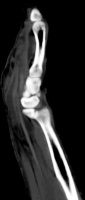

The radiologist  interpreted his MRI as normal, but these views show bulky, edematous flexor synovitis.